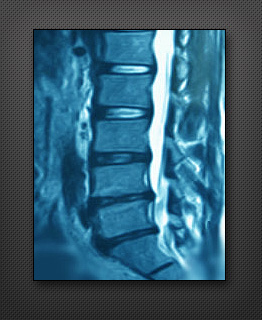

허리디스크

인체의 척추는 30여 개의 뼈가 쌓여있는데, 그 척추뼈 사이에는 물렁뼈 조직인 추간판(디스크)이 있습니다.

추간판은 외부로부터 척추에 가해지는 충격을 완화시키고 척추뼈 각각의 움직임을 원활하게 함으로써 척추가 제 기능을 수행할 수 있도록 도와주는 역할을 합니다.디스크 질환은 섬유질과 수핵으로 구성되어 있는 디스크가 외상이나 변성에 의하여 섬유륜이 찢어져 그 사이로 수핵이 빠져나와 신경을 누르는 질환입니다.이런 경우 가벼운 외상이라도 받는다면 수핵이 터져 신경을 자극하는 디스크 병이 됩니다.특히 허리디스크는 요추의 디스크가 밀려나와 하반신으로 흐르는 신경을 압박하므로 묵직한 느낌의요통과 함께 당기거나 저리는 통증이 엉치에서 다리, 발까지 나타나게 됩니다.간혹 극심한 통증으로 하반신을 움직이기 어려운 운동제한이 갑자기 나타나기도 하므로 평소 만성적인 요통과 함께 다리나 발의 저림, 당김 증상이 미세하게 느껴진다면 더욱 주의를 기울여야 합니다.